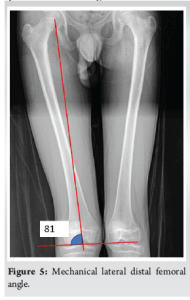

A 16-year-old boy presented to our outpatient department with a history of recurrent patellar dislocation in his right knee for the past 3 years. He also complained of a deformity of his right knee. On examination, his patella was grossly unstable, dislocating at about 30° of knee flexion (Fig. 1). Whole limb X-ray revealed a lateral mechanical axis deviation of 30 mm from the neutral (normal range – <10 mm) (Fig. 2). The opposite limb was normal. The Q angle of the right lower limb was measured to be 22°, which was abnormal (normal range 13–18°). The right knee was in valgus with a tibio-femoral angle of 15° (Fig. 3). The mechanical medial proximal tibial angle was 87.8° which was normal (normal range 85–90). However, the mechanical lateral distal femoral angle was 81°, which was abnormal (normal range 85–90) (Fig. 4 and 5). Hence, it was the distal femur that contributed to the genu valgum. The tibial tubercle–trochlear groove distance was 17 mm, which was normal (normal – under 20 mm), signifying that there was no rotational deformity. The Insall-Salvati ratio was 1.2, which was also normal (range – 0.8–1.2). Magnetic resonance imaging (MRI) revealed a Dejour Type D trochlea dysplasia (Fig. 6) with a trochlear depth of 1.2 mm (normal >3 mm) and a sulcus angle of 172 (normal <140). MRI also revealed an MPFL tear. The factors contributing to the patellar instability were recognized as the unacceptable genu valgum, trochlear dysplasia, and the MPFL tear. Considering that the patient had attained skeletal maturity and to avoid multiple procedures, a decision was made to correct all the anatomical abnormalities as a single procedure.